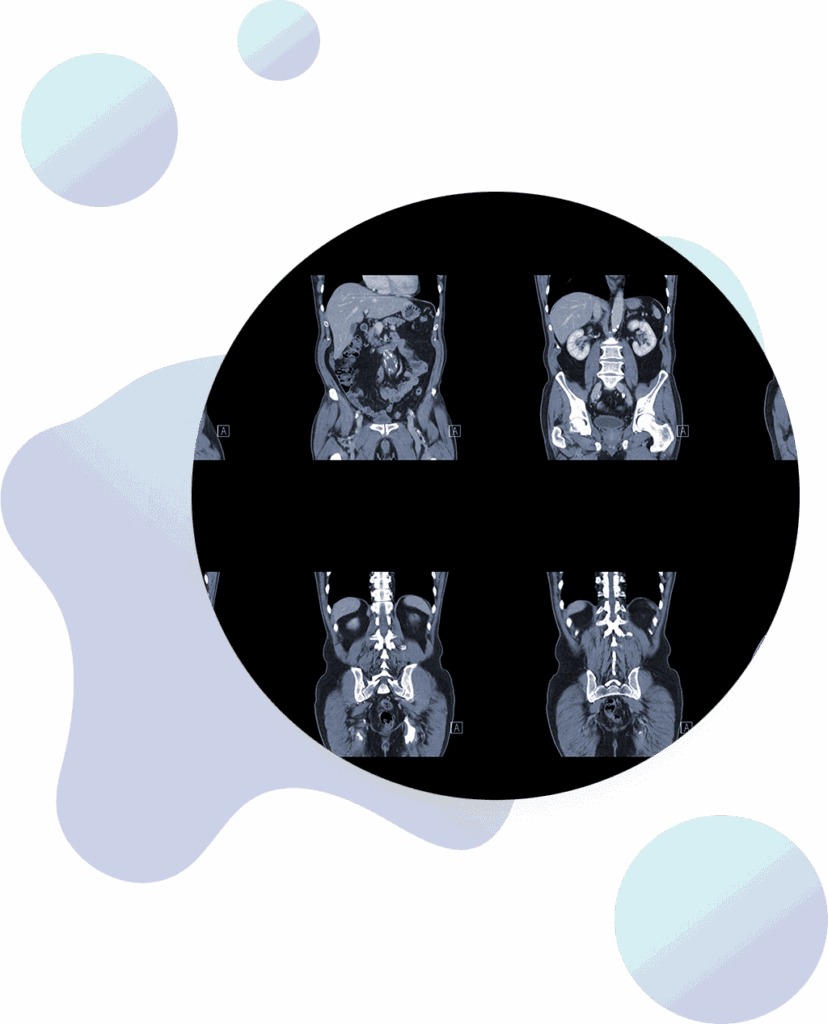

CT scans

Computed tomography (CT) scans are a more advanced type of X-ray. Executive Medicine of Texas uses CT scans to screen for lung cancer and heart disease. They also diagnose abnormalities of the kidneys, liver, and pancreas,

Virtual colonoscopy (colonography)

3D virtual colonoscopy uses a CT scan to diagnose colon cancer early on when it’s easiest to treat. Unlike traditional colonoscopy, virtual colonoscopy requires no anesthesia. As a result, you can return to work and other activities immediately after your appointment.